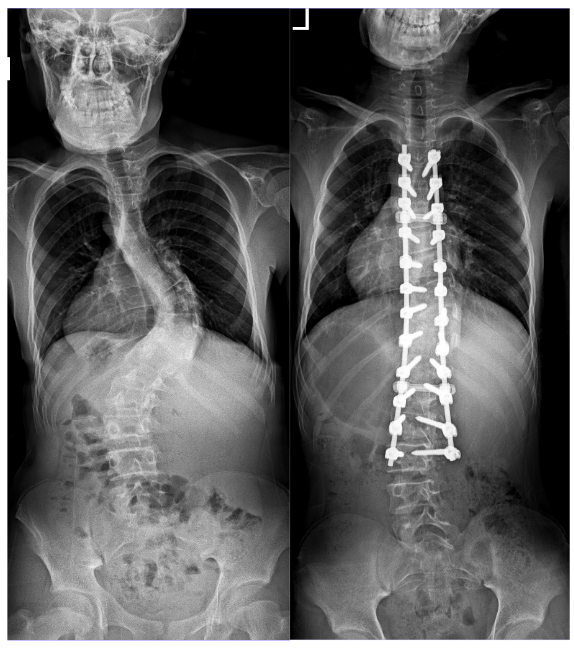

4月16日,华西天府医院骨科收治了石曲两兄弟。入院后询问病史得知,两兄弟多年前便出现胸背部高低不平,双肩不等高,身高增长不明显等问题。影像学显示:两兄弟脊柱呈“S”形侧弯畸形,双肩不等高,胸椎向右侧弯,腰椎向左侧弯,可见明显“剃刀背”畸形。其中一人并存肌性斜颈。

手术过程中,宋跃明教授、汪雷副教授运用了“经后路侧弯顶椎区多节段椎间盘切除、椎间隙松解+多节段SPO(Smith-Petersen Osteotomy)截骨技术,提高了僵硬型侧弯的柔韧性,再辅以华西脊柱侧弯撑开矫形去旋转工具,在保证脊髓神经安全的前提下,实现脊柱的三维畸形矫正,两位患者的侧弯矫正率分别达到了86%和78%,胸背部后凸畸形也得到了较好的矫正。

患儿2术前、术后影像资料

术后复查X光显示:脊柱侧凸和后凸畸形得到有效纠正,两患儿的身高分别增加了8-10cm,经宋跃明教授、汪雷副教授多次查房评估,两患儿恢复良好,并于5月8日顺利出院。